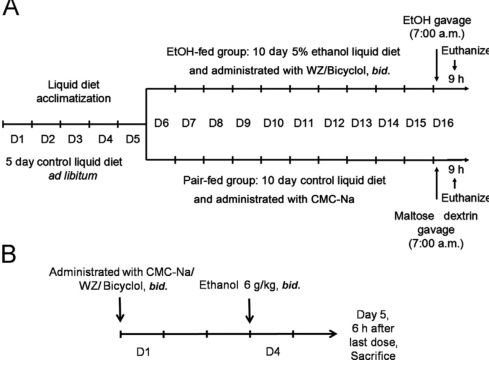

二、实验步骤

- 动物准备:大鼠适应性饲养5天,自由摄食饮水。随后随机分为模型组与对照组,每组至少8只。对照组灌胃等体积生理盐水或蒸馏水。

- 酒精溶液配制:根据实验需求,将无水乙醇或食用酒精与蒸馏水按一定比例混合,配制成不同浓度的酒精溶液。常用浓度范围从5%至35%(V/V)不等。

- 灌胃操作:按照预定的剂量和浓度,将酒精溶液通过灌胃针缓慢注入动物胃内。灌胃剂量通常根据动物的体重计算,如小鼠常用剂量为10ml/kg体重。灌胃频率和持续时间也需根据实验需求进行设定,如每天灌胃1次,持续数周至数月。

- 模型观察采样:在灌胃过程中和灌胃结束后,密切观察动物的行为学变化、体重变化、毛发色泽改变及精神状态等一般情况。每周称重,记录摄食量及精神状态;造模4周后禁食12 h,麻醉下心脏采血分离血清;取肝、脑组织,部分福尔马林固定(病理切片),部分液氮速冻(分子检测)。

- 干扰因素:昼夜节律影响乙醇代谢,灌胃需固定于清晨(7:00–9:00),此时血醇浓度峰值更高。